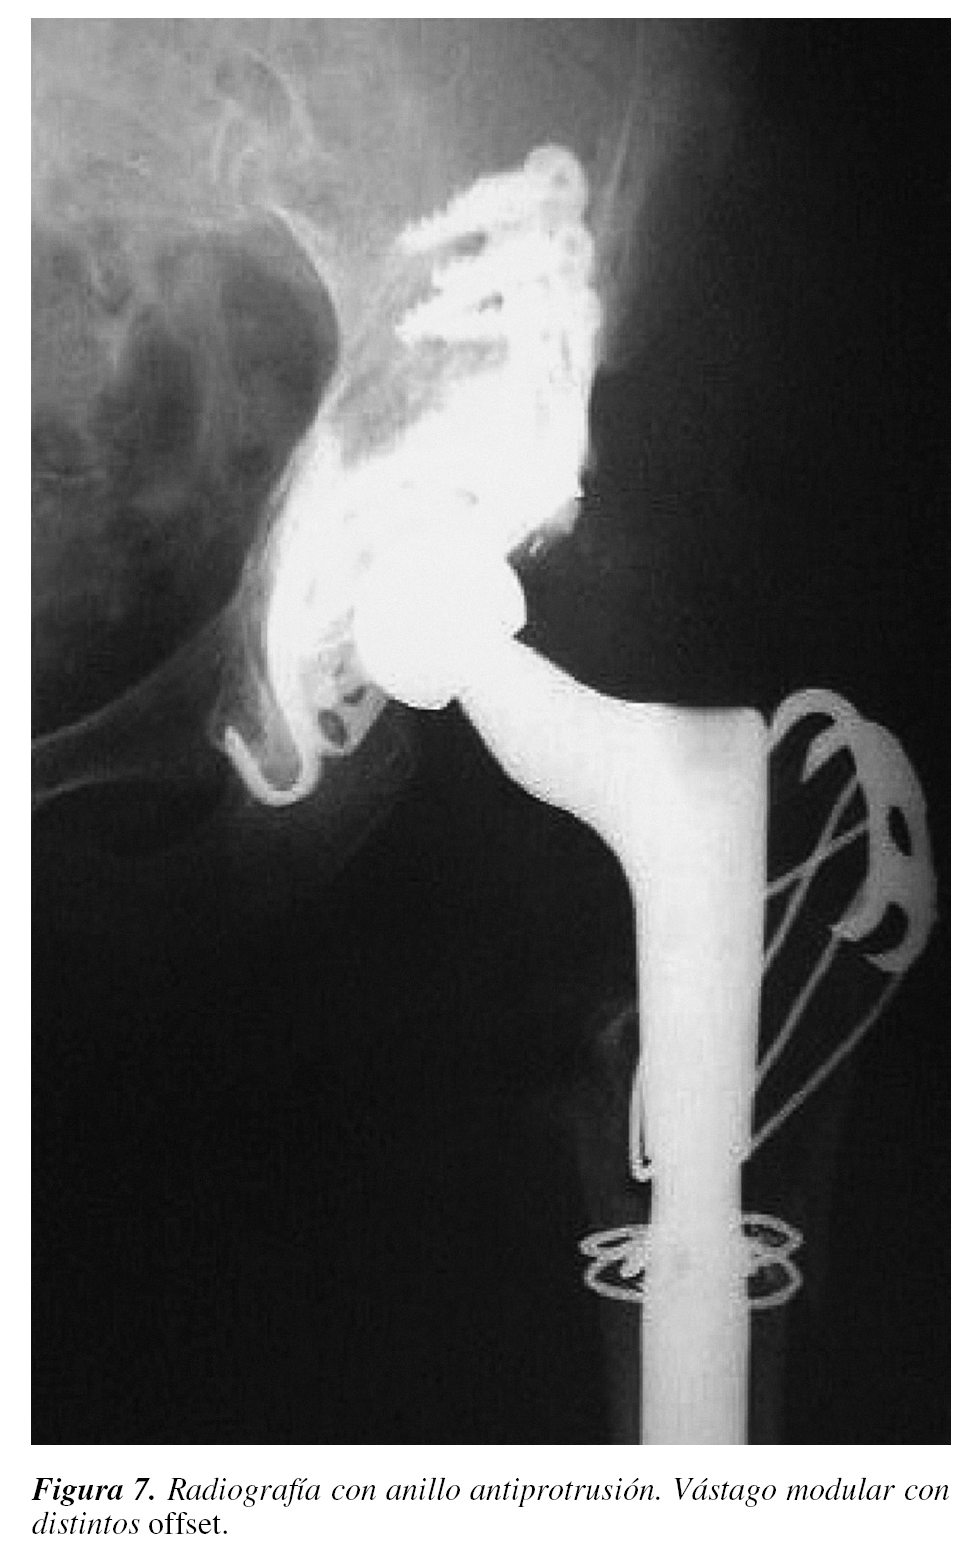

TRATAMIENTO DE LA INADECUADA TENSIÓN

DE PARTES BLANDAS

El restablecimiento de la tensión de las partes blandas es fundamental para mantener la estabilidad de la cadera. La avulsión y ascenso del trocánter mayor osteotomizado supone un riesgo, por lo que se ha aconsejado la reinserción profiláctica del mismo, descendiéndolo y adelantándolo para limitar la rotación interna. Sin embargo22 el 80% de las prótesis luxadas, que presentaban ausencia de unión del trocánter, permanecieron estables después de la reducción cerrada inicial, por lo que la reinserción del mismo parece aconsejable sólo si se producen recidivas (fig. 7).

Ekelund26 publica que el descenso del trocánter mayor, esté o no bien fusionado, y su reinserción más distal con el miembro en abducción han mostrado resultados satisfactorios en la estabilización de la prótesis, sin defectos de orientación en 19 de 21 pacientes. En el estudio se incluyen 7 casos de ATC tras osteosíntesis fracasada en fracturas subcapitales, que se sabe que constituyen un grupo de alto riesgo de inestabilidad. Se recomienda igualmente sistemas modernos de fijación como las grapas con cables de Dall-Miles, dada la frecuentemente escasa consistencia de la estructura ósea en esta zona.